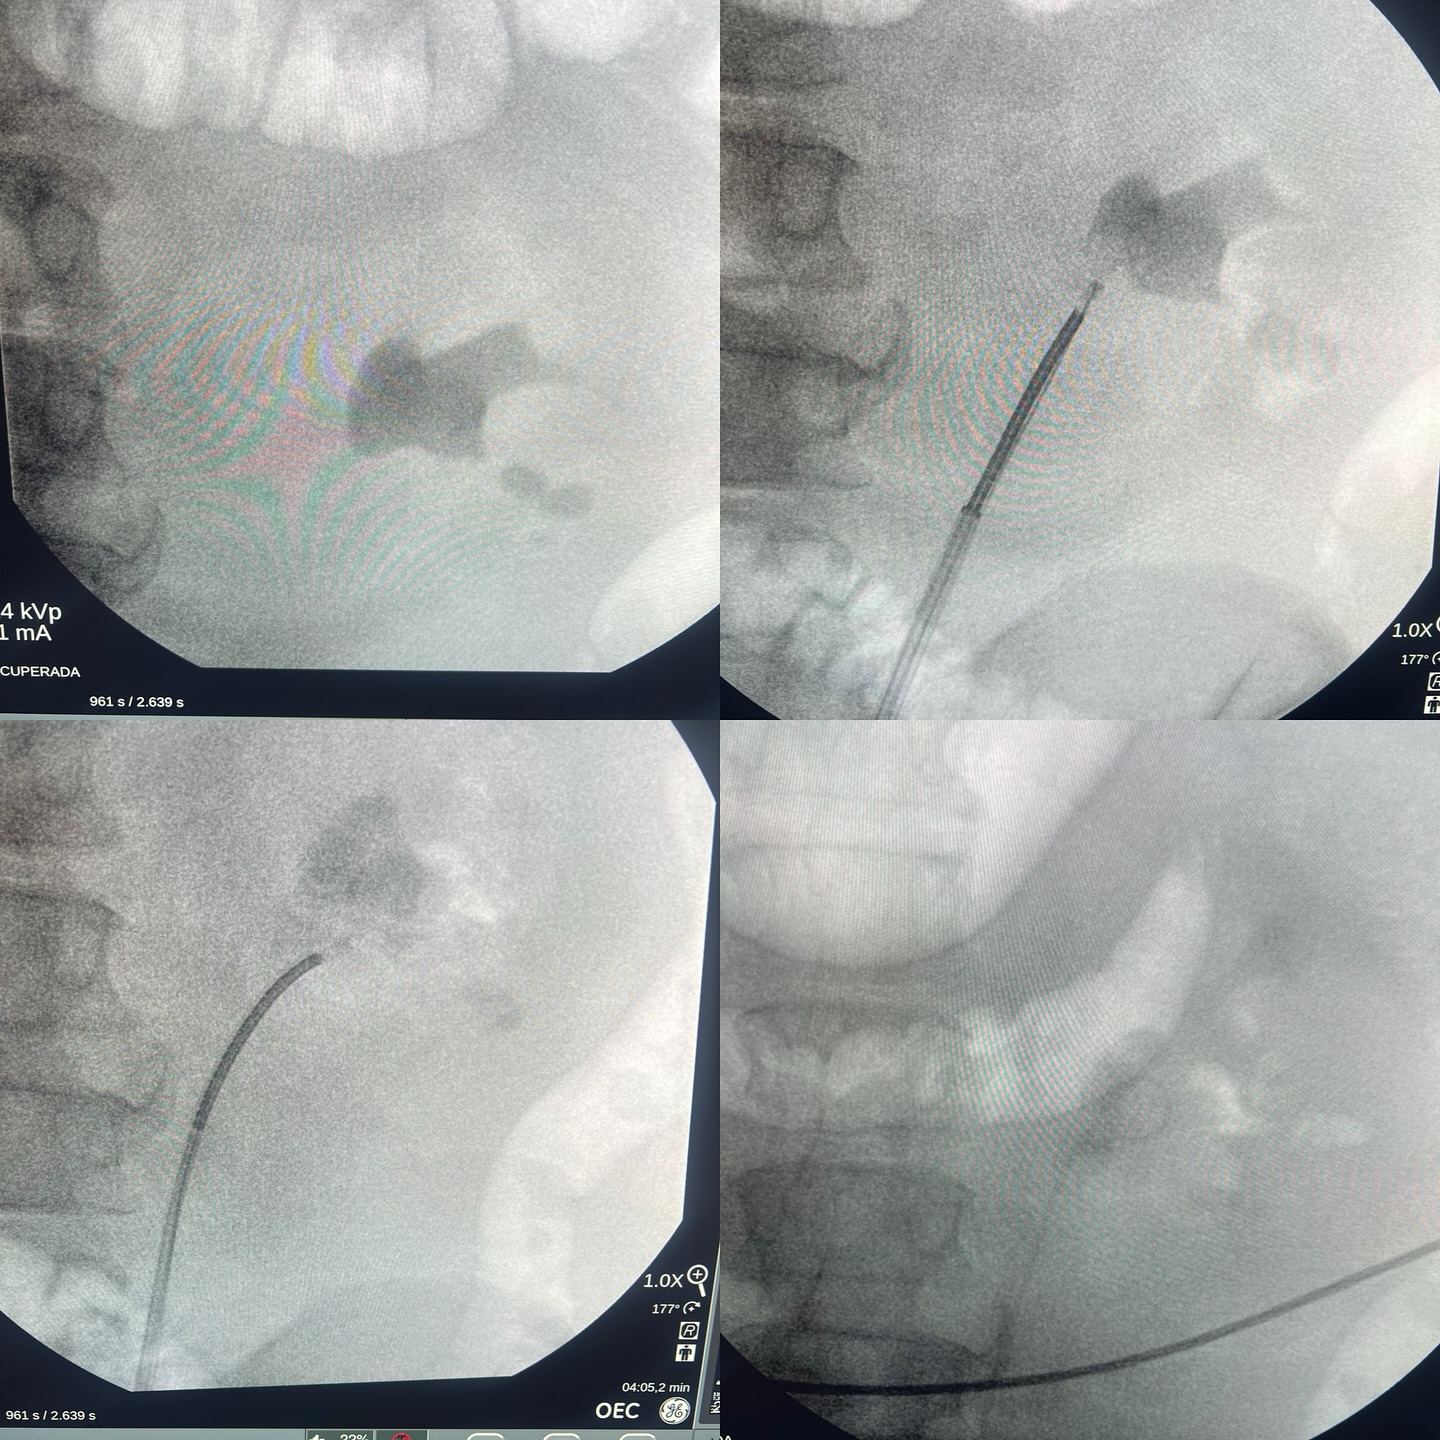

Atendimos un caso muy interesante: paciente masculino de 58 años con obesidad mórbida, enfermedad pulmonar y cardíaca.

El paciente presentaba un cálculo renal de gran tamaño, y aunque la cirugía ideal hubiese sido una nefrolitotomía percutánea, sus condiciones médicas representaban un alto riesgo.

Optamos por una alternativa menos invasiva y efectiva: una ureteroscopía flexible, utilizando el ureteroscopio LithoVue de Boston Scientific y el Holmium Láser de alta energía; 150W.

El resultado: logramos fragmentar y extraer aproximadamente el 95% del cálculo renal, todo mediante una técnica mínimamente invasiva.

El remanente será removido en una segunda intervención planificada.